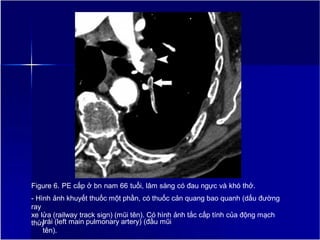

Figure 6. PE cấp ở bn nam 66 tuổi, lâm sàng có đau ngực và khó thở.

- Hình ảnh khuyết thuốc một phần, có thuốc cản quang bao quanh (dấu đường

ray

xe lửa (railway track sign) (mũi tên). Có hình ảnh tắc cấp tính của động mạch

thùy

trái (left main pulmonary artery) (đầu mũi

tên).

Tiếp tuyến của huyết khối (đường liên tục)

và tiếp tuyến của thành mạch (đường

không liên tục) tạo thành góc nhọn.